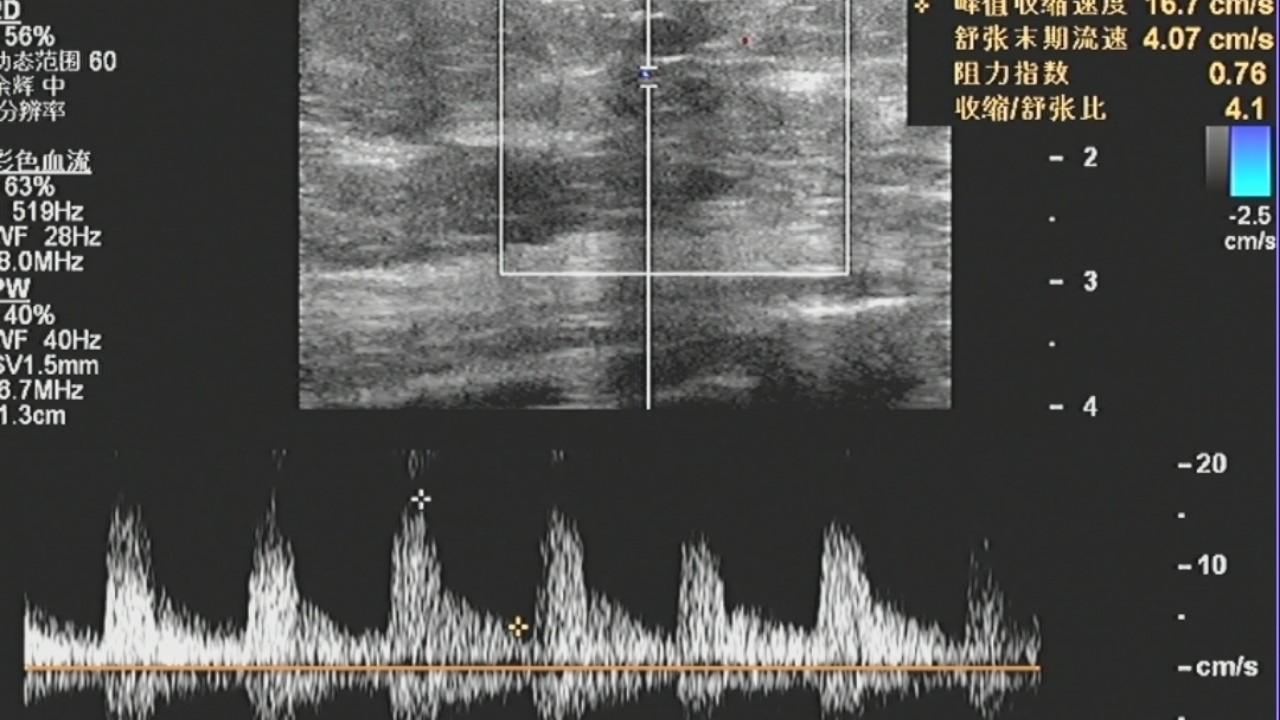

6、肿块内血流丰富,不规则,多为高频、高阻血流。